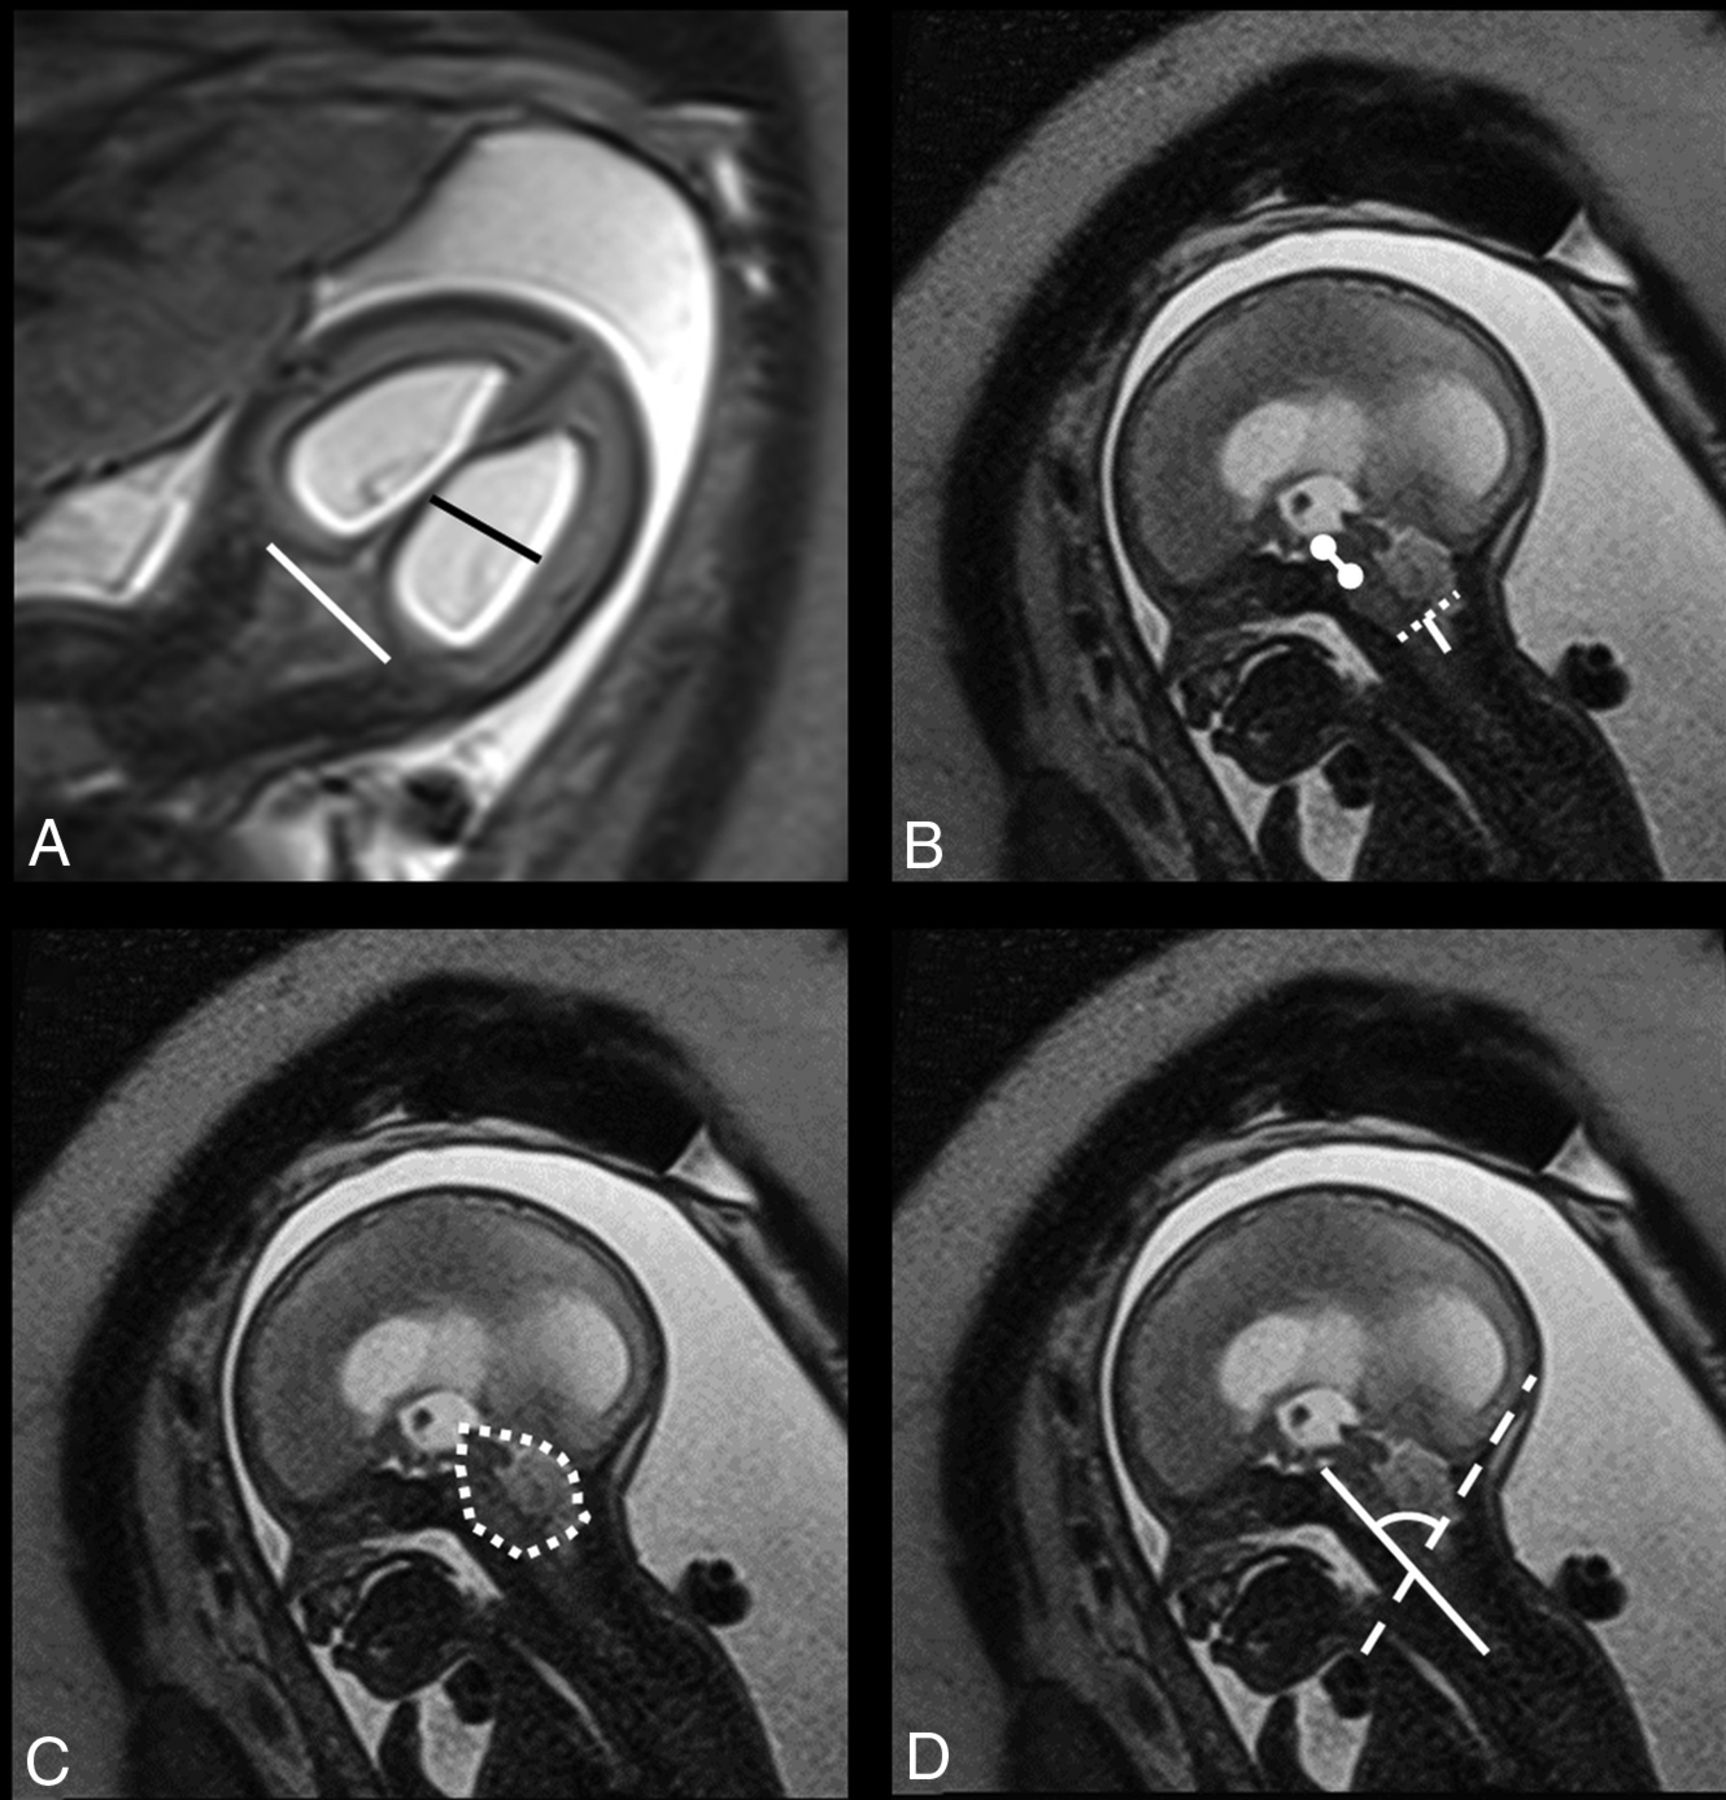

Biometric variables included the transverse cerebellar diameter (TCD), pontine thickness, and pontine height, measured according to the standards defined by Garel26 and Tilea et al.27 The transverse diameter of the PF (TDPF) was measured according to Woitek et al,17 who suggested that this would be a proxy for the TCD. The midsagittal PF area was measured according to Tsai et al.20 The ventricular width (VW) was measured in the coronal plane according to Garel,26 and in case of asymmetry, the largest value was taken into account. Mamillopontine distance, the level of kinking of the brain stem, medullary length, tentorial length, and width of the cisterna magna were measured as described by Geerdink et al.8 The width of the foramen magnum was defined as the distance between the opisthion and the basion. The cerebellar herniation level (CHL) was measured by drawing a perpendicular line from the foramen magnum to the lowest cerebellar portion. In the presence of cerebellar herniation, the deepest portion was measured.20 The clivus-supraocciput angle (CSA) was measured according to D'Addario et al.28 The TCD, TDPF, mamillopontine distance, TL, PF area, and CSA are demonstrated in Fig 1.

T2-weighted imaging (HASTE) in the coronal (A) plane shows the biparietal diameter (white line in A) and the ventricular width (black line in A). In the sagittal plane (B–D), the mamillopontine distance (white line with circles at both ends in B) is demonstrated along with the foramen magnum diameter (dotted white line in B) and the cerebellar herniation level (white line perpendicular to the dotted line in B). The midsagittal posterior fossa area is shown in C (dotted free form), and the clivus-supraocciput angle is demonstrated in D with a line according to the clivus (white line) and the occiput (dotted line).